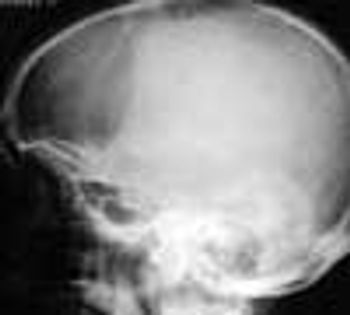

Skull x-ray films were taken after this 62-year-old nursing home resident fell and hit his head. The radiographs revealed only a sharply demarcated radiolucent area, mainly over the right parietal bone. Osteoporosis circumscripta was diagnosed.